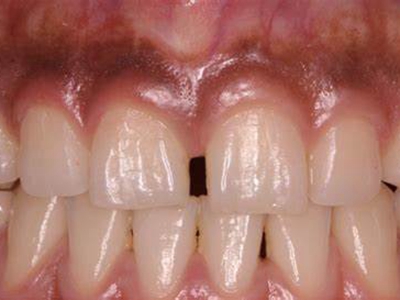

牙龈退缩牙根暴露出现黑斑图

牙龈退缩患者的上排多颗牙齿处的牙龈出现回缩,从而导致牙根外露,外露的牙根上存在黑色的牙菌斑、牙结石,伴有口臭、牙根面敏感等症状。